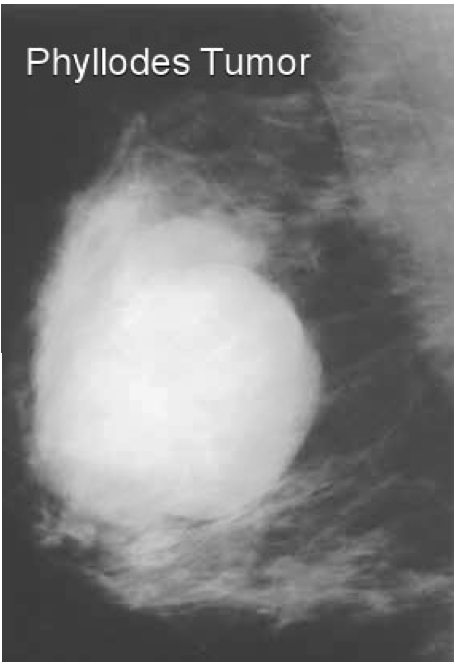

What is the name of a large fibroadenoma that grows rapidly? Why is this concerning

Phyllodes tumor

Can be malignant

How do you treat a Phyllodes Tumor

Excision required